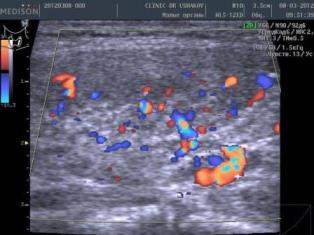

| В левой доле (в сосудистом режиме; ЦДК) заметна умеренная интенсификация кровотока ― свойственно избыточному напряжению железы |